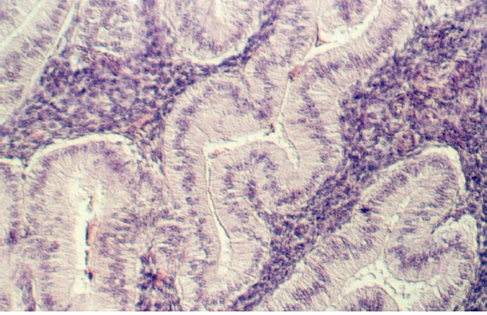

Slide 86 shows a uterus in the proliferative phase. The endometrium is illustrated in the photograph below. Note that the cells are low columnar to high columnar. The glands are relatively straight with a narrow lumina. Outside the glands is the highly cellular lamina propria. The following photos illustrate the proliferative phase with higher magnifications.

After ovulation, the uterine lining becomes more tortuous. The lining is now under the control of progesterone. This steroid hormone stimulates the lining to secrete material that may help nourish both sperm and a potential pregnancy. The glands expand and the lumina are wide and contain products of secretion. The glandular epithelium may be characterized by a droplet of secretory material under the nucleus (near the base) about 2 days after ovulation (day 16). Then, the secretory products move more towards the lumen. Slide 87 shows the Secretory phase of the uterine lining. Note the sections showing coiled or tortuous glands and the dense lamina propria.